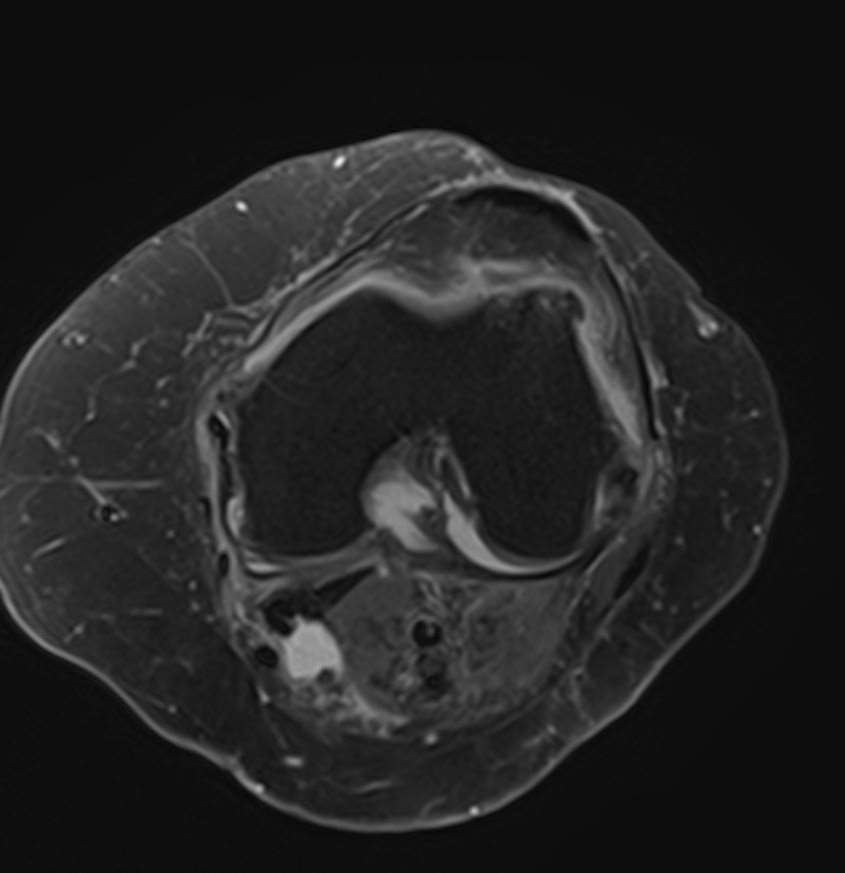

При сочетанном поражении этих анатомических областей целесообразно проведение комплексной МРТ, включающей обследование пояснично-крестцового отдела позвоночника и коленных суставов.

Магнитно-резонансная томография является высокоинформативным методом выявления причин возникновения заболеваний позвоночного столба и суставов. В клинике «Доступная медицина» диагностика осуществляется на новейшем высокопольном томографе закрытого типа TOSHIBA VANTAGE TITAN 1,5 Тесла, обеспечивающем высочайшее качество изображений исследуемой зоны.

Томограф позволяет детально визуализировать состояние всех анатомических структур позвоночного столба на исследуемом уровне, костные структуры колена и окружающие мягкие ткани данных анатомических областей, включая мышцы, связки, нервные сплетение, сосуды.